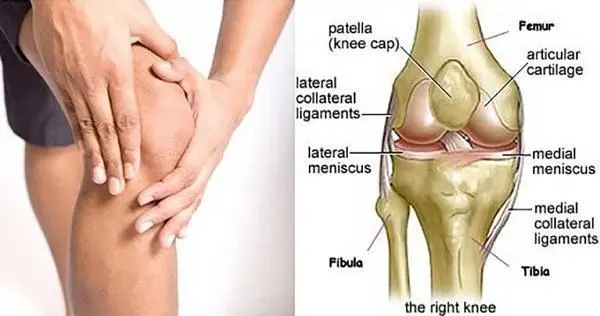

العظام

حيث يوجد في الركبة ثلاث أجزاء من العظام وهم:

- عظم الفخذ: ويسمى عظام الفخذ العلوي وتتصل في نهايتها بعظم الساق.

- عظام الساق: وهو عظام الساق السفلي وتسمى (الظنبوب).

- الرضفة: ويطلق عليها صابونة الركبة وتوجد أمام المفصل وفوق عظم الفخذ.

الأربطة

يوجد نوعان من الأربطة وهما:

- الرباط الصليبي الأمامي والخلفي: حيث تساعد في حركة الركبة والمحافظة على استقرارها.

- الأربطة الجانبية: حيث توجد على جانبي الركبة وتعمل على تثبيتها وهما ( الإنسية والجانبية).

الغضاريف

- الغضاريف الهلالية: يكونان على شكل هلال، وتتمثل وظيفتهما في امتصاص الصدمات التي يتعرض إليها الشخص، كما أنها تعمل على تحسين توافق العظام.

- الغضروف الزجاجي: حيث يعمل هذا الغضروف على تقليل الاحتكاك وتسهيل الحركة أيضًا ويوجد في نهاية العظام.